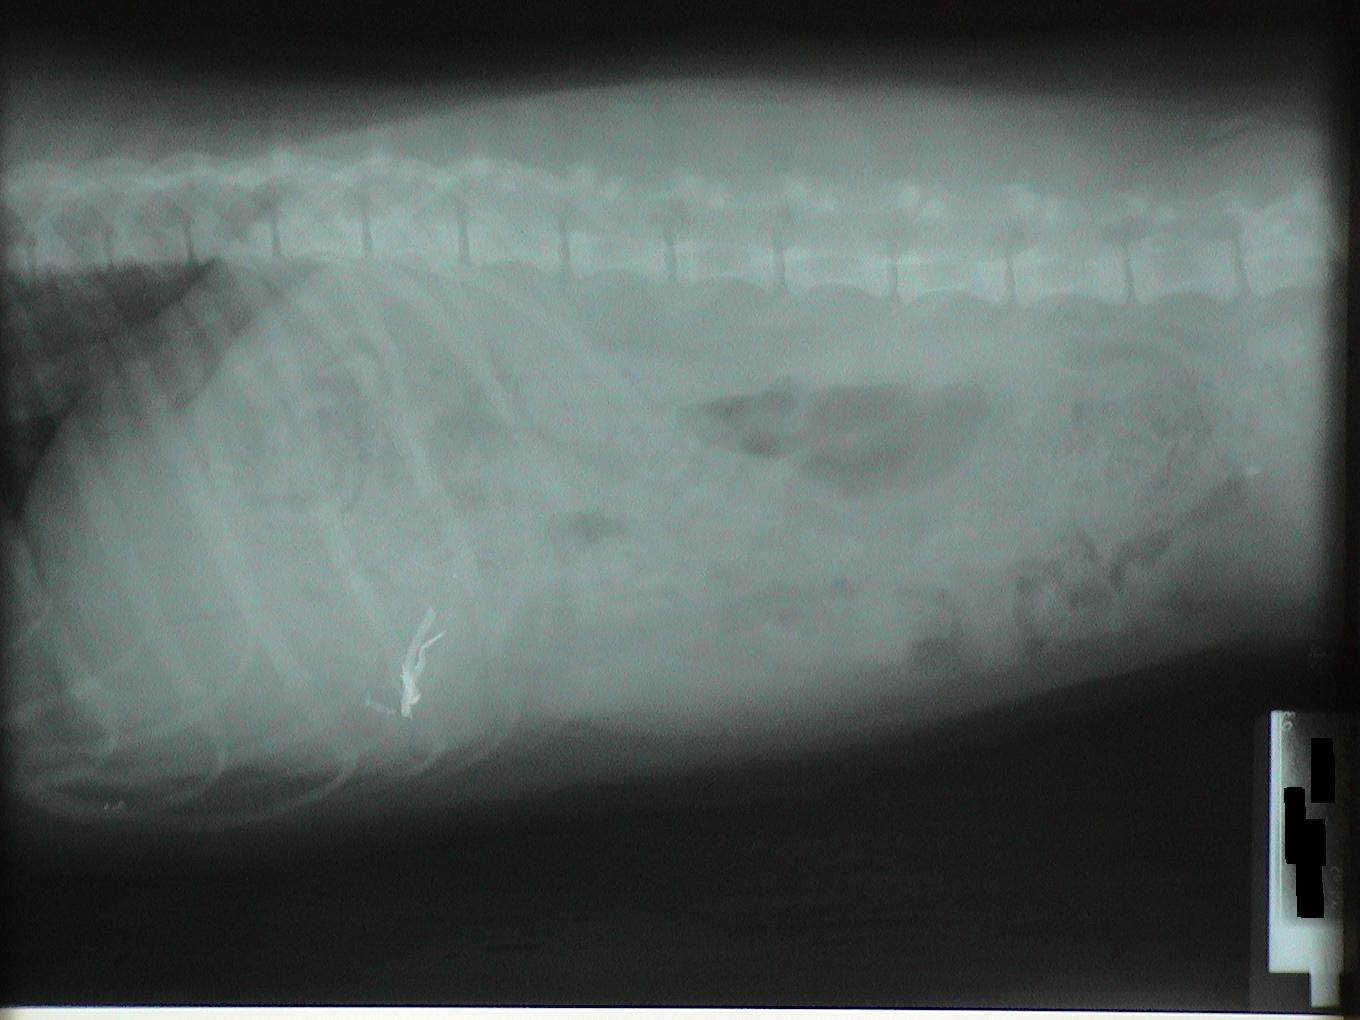

Let's identify the foreign bodies in each of these x-rays.

This is a trick question. This is a pregnant dog. Each skull is circled in blue.